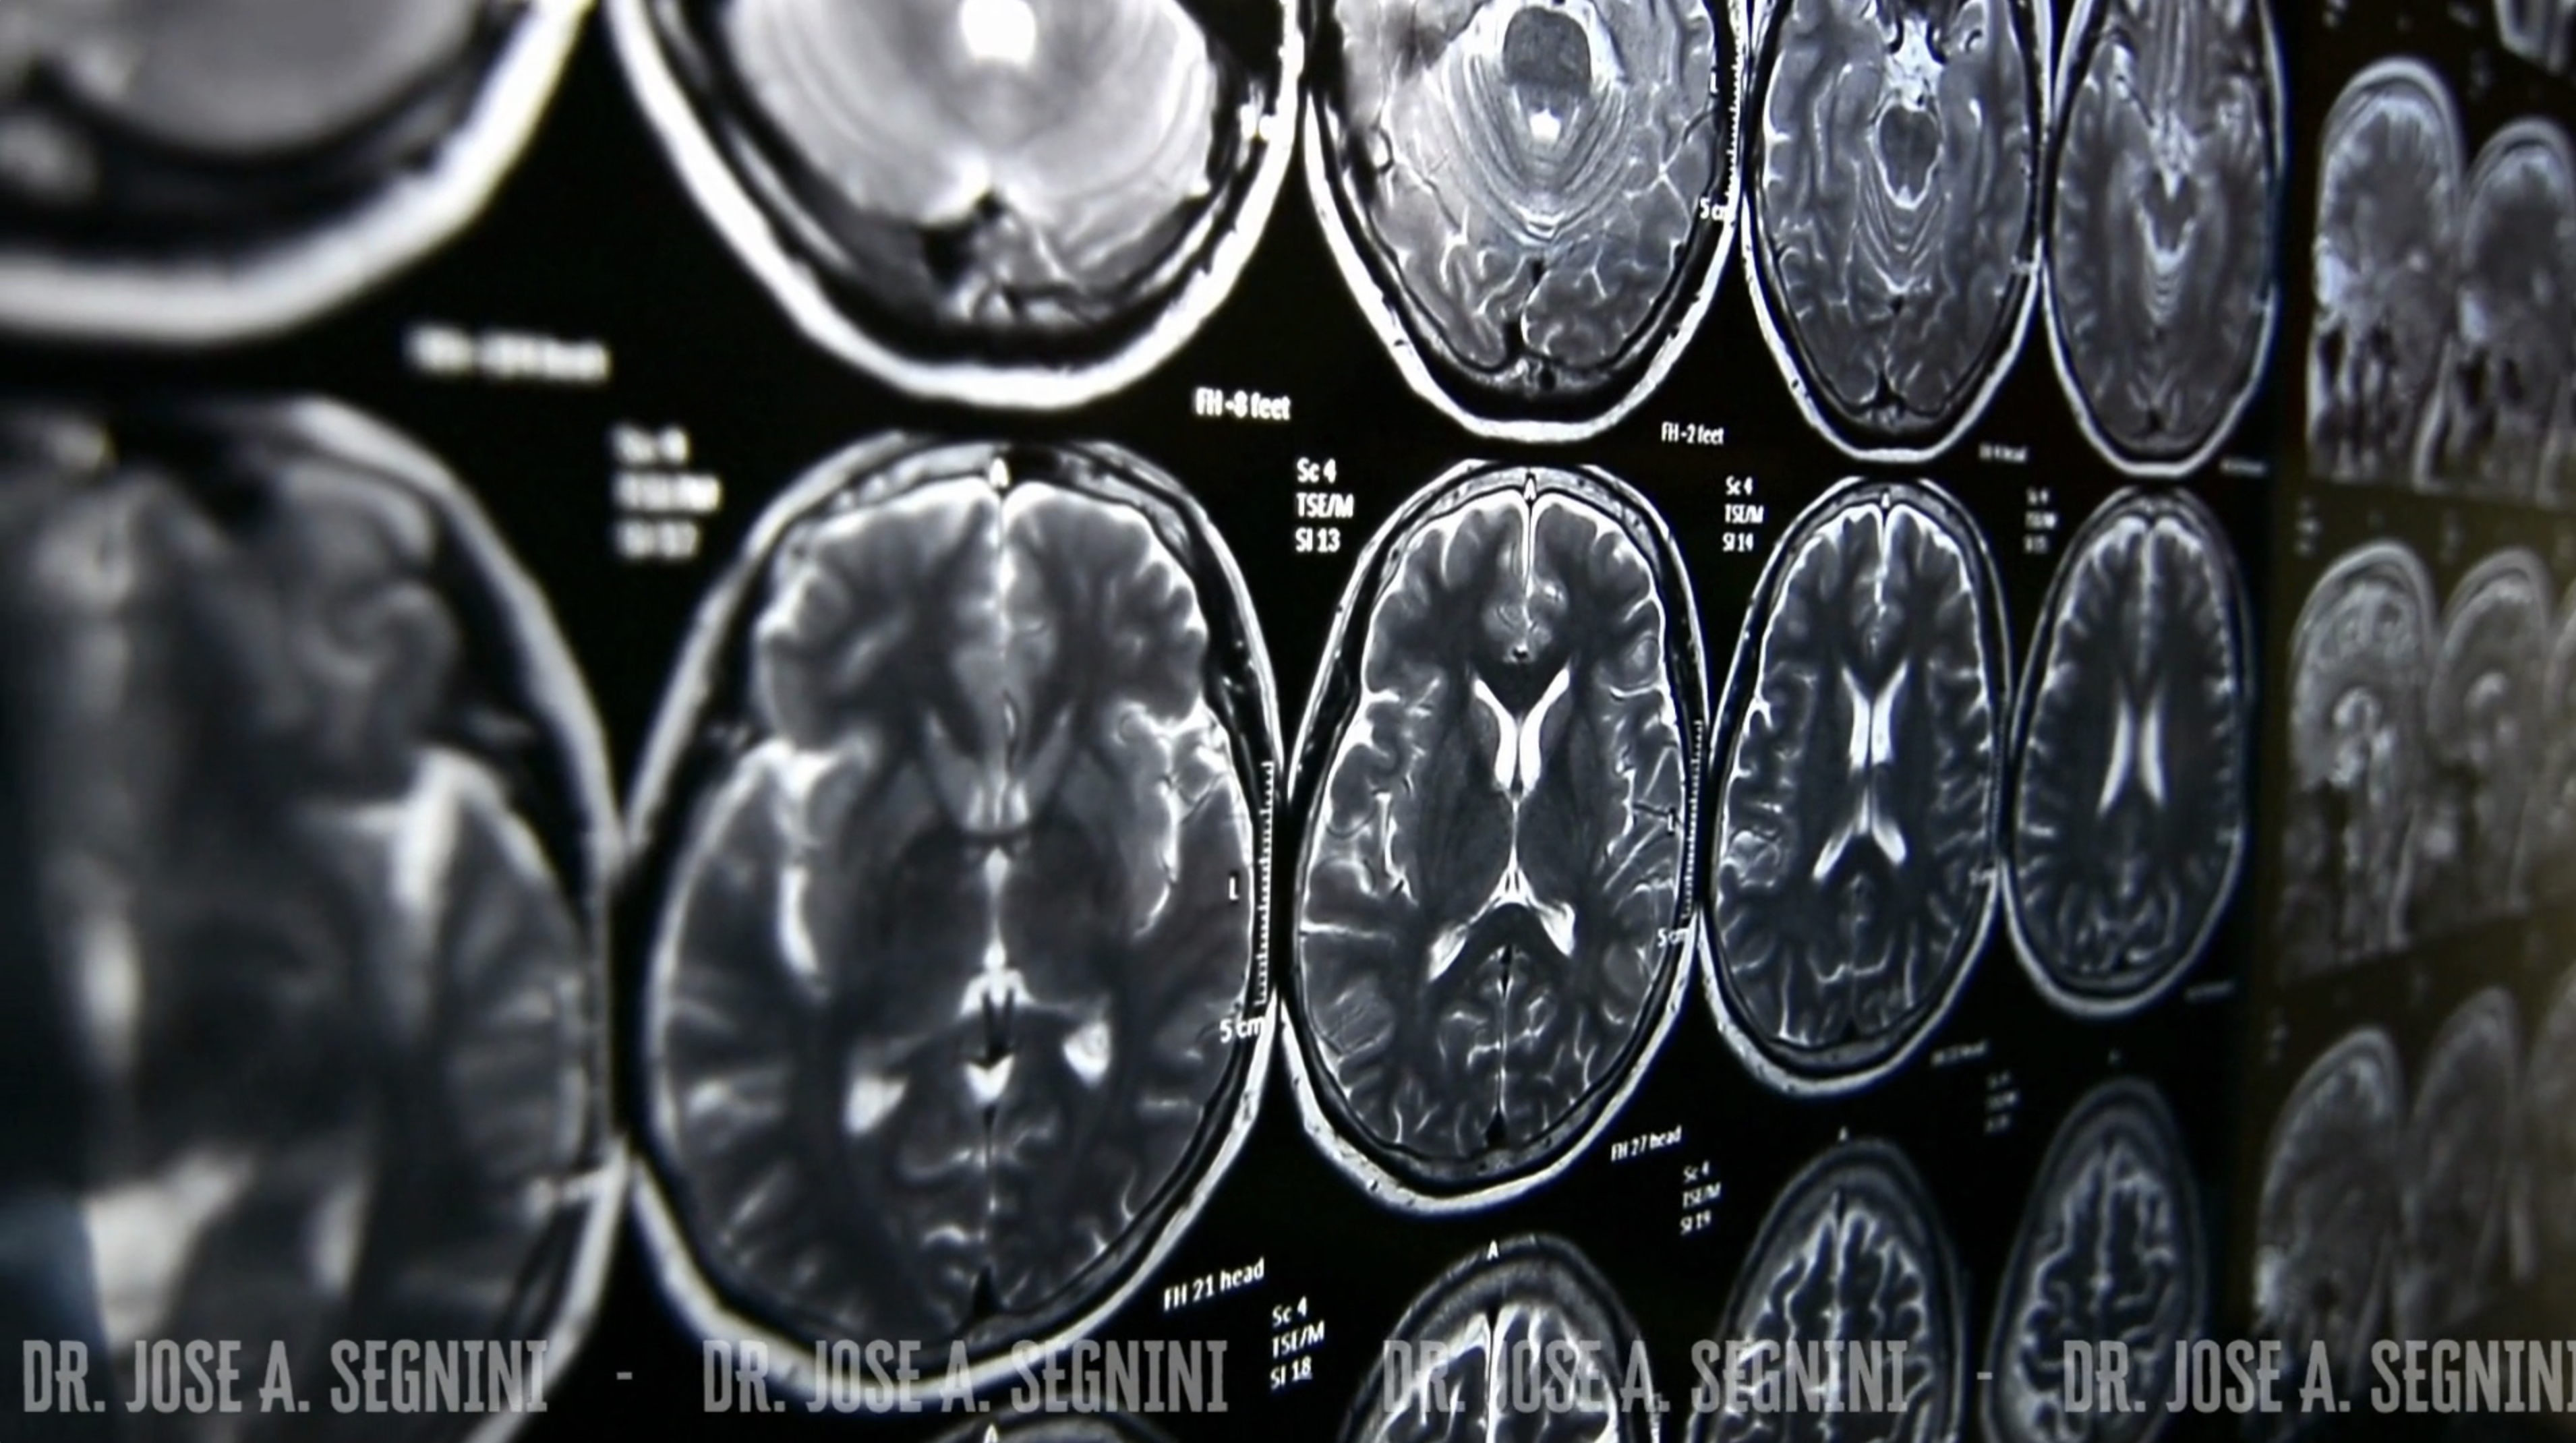

TELERADIOLOGIA

Sistemas de última tecnología para visualizar imágenes DICOM, gestionar servicios de radiología (RIS/PACS).

- Resonancia Magnética Nuclear